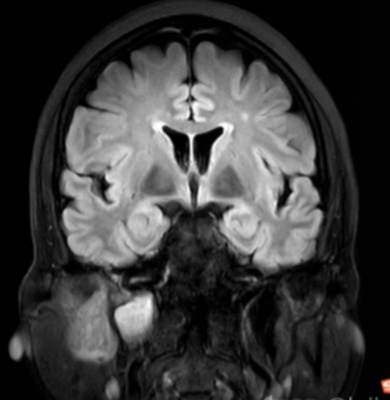

(2023-05-15 10:00,本院)行磁共振(颅脑)检查提示:右侧乳突区异常信号,考虑恶性、软骨来源肿瘤,软骨肉瘤可能性大。(集体讨论意见);脑内散在多发缺血灶。

(2023-05-12 10:15,本院)行CT(颅脑)检查提示:右侧颞骨广泛骨质破坏,伴巨大软组织肿块,性质待定,考虑肿瘤性病变,颈静脉球瘤?软骨源性肿瘤?请结合临床及病理进一步明确。